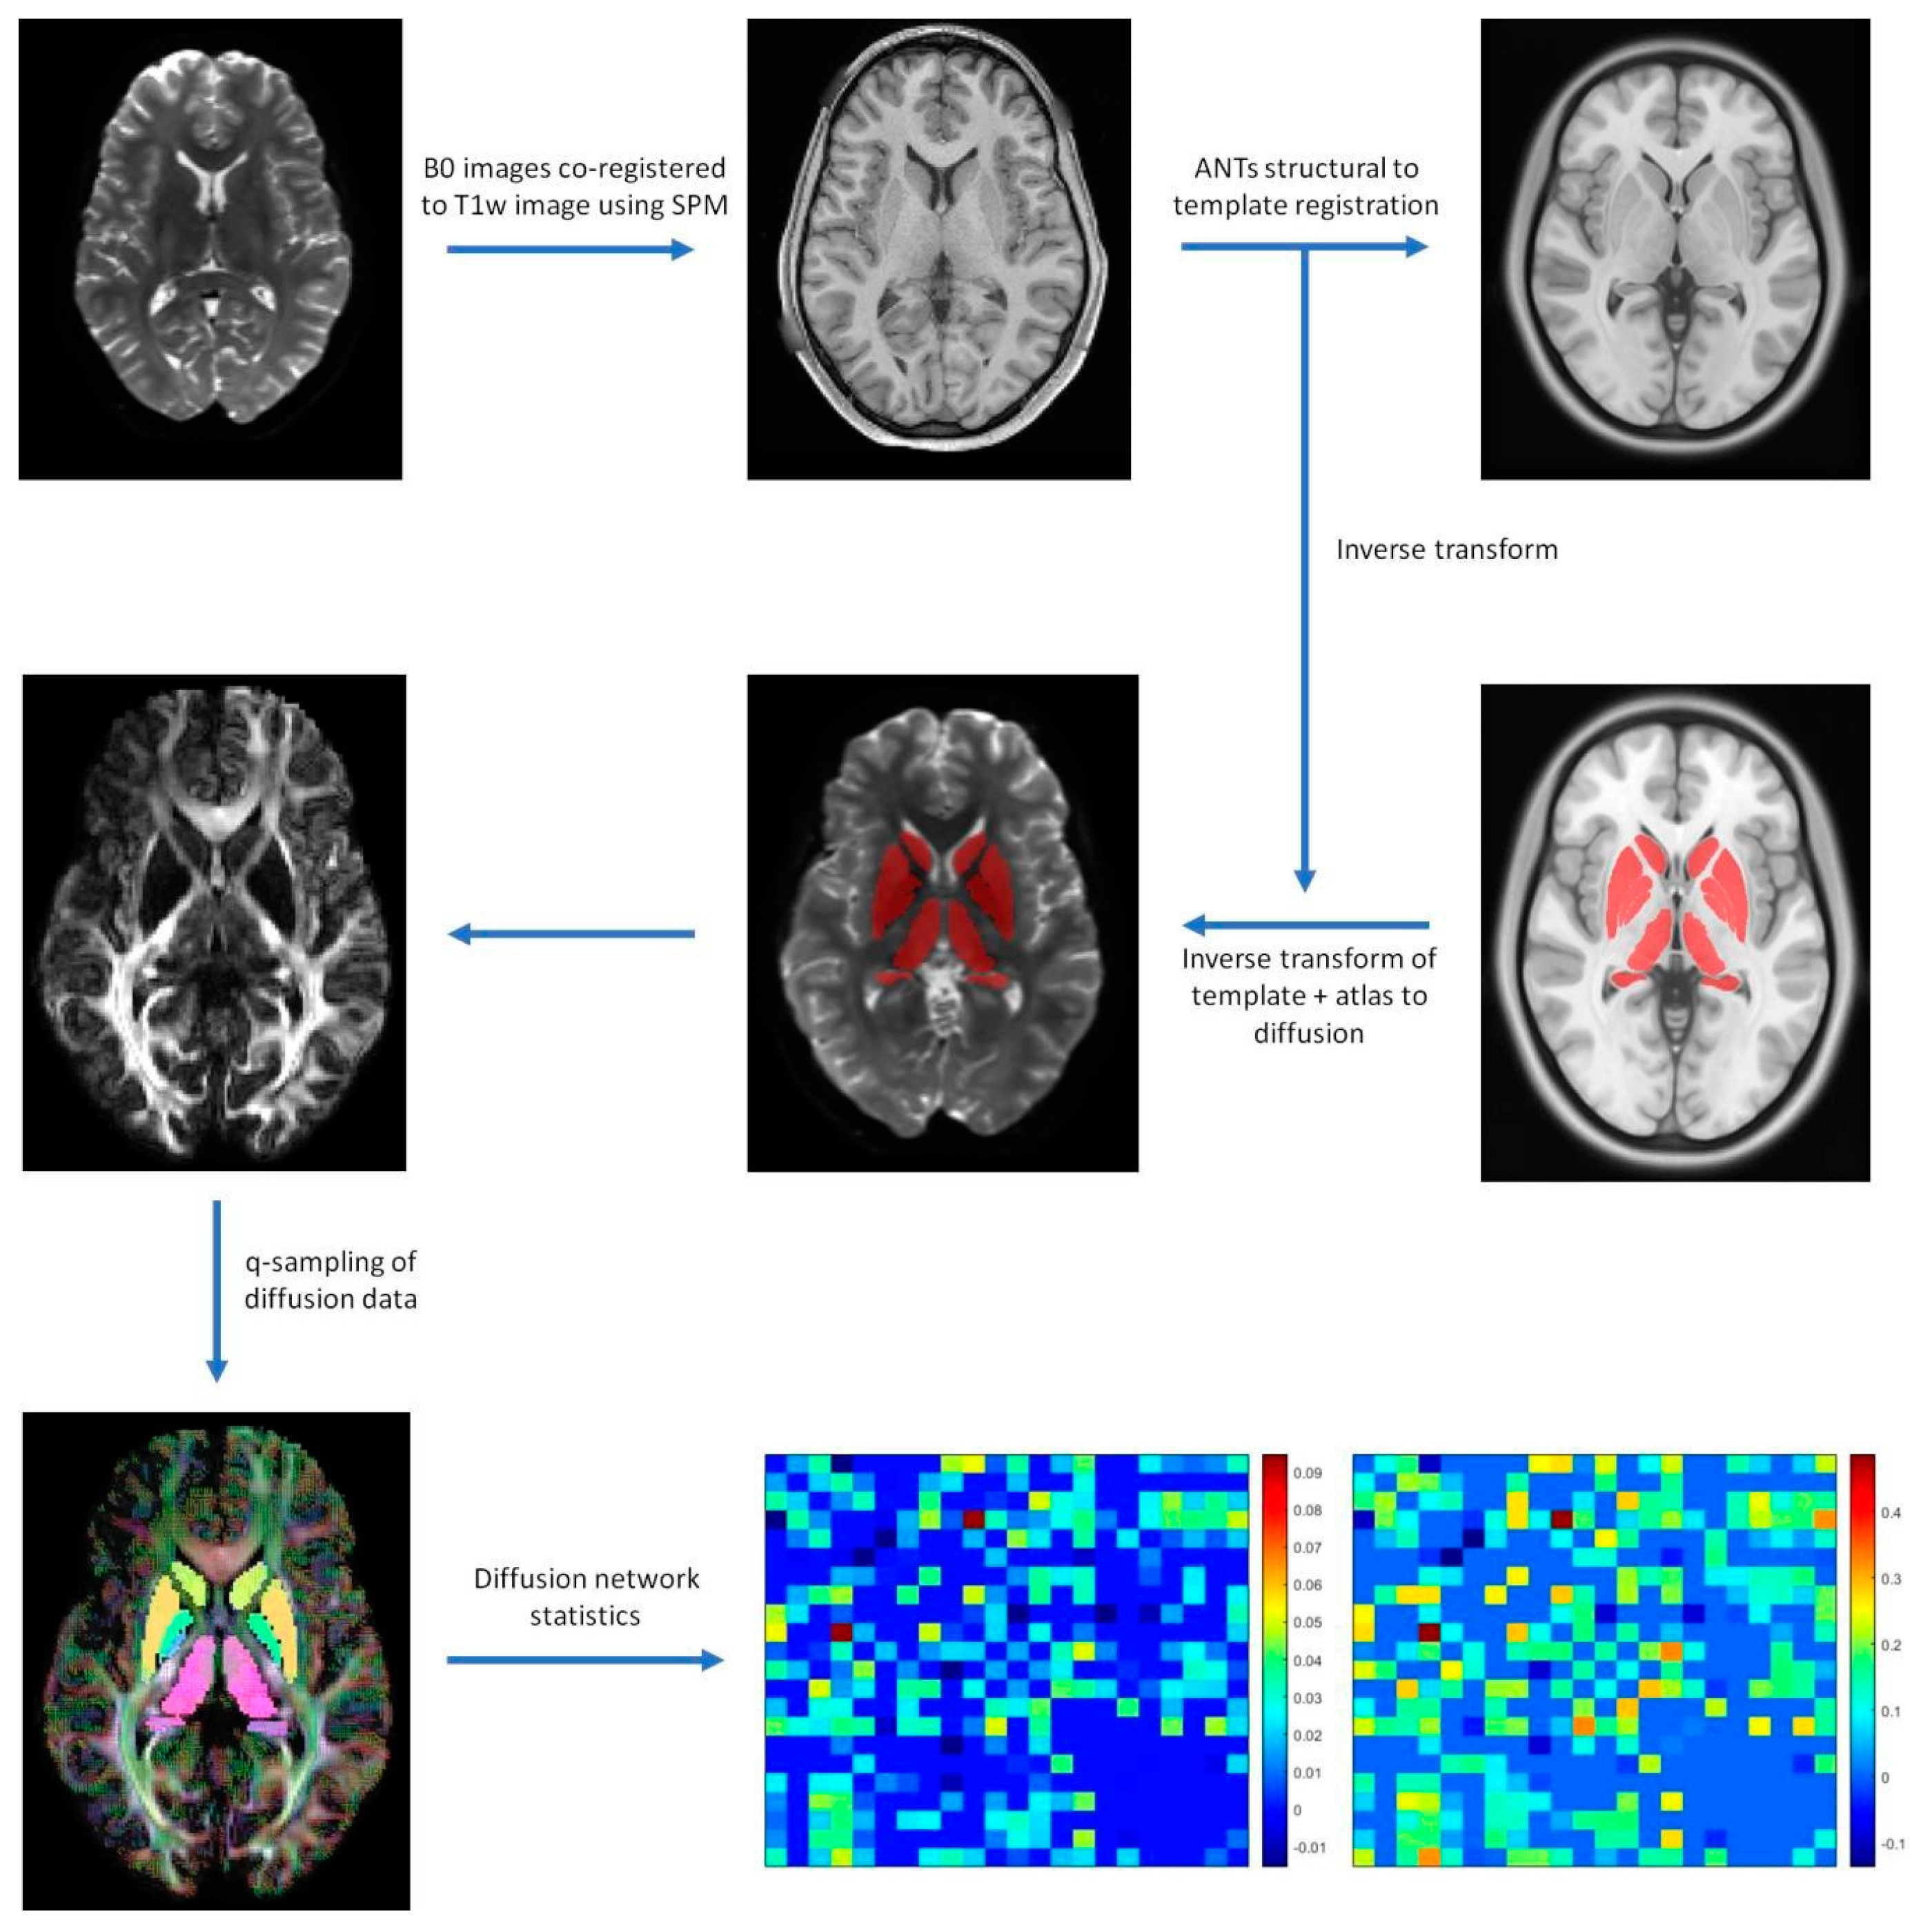

2.3. Image Processing

2.4. Diffusion Processing